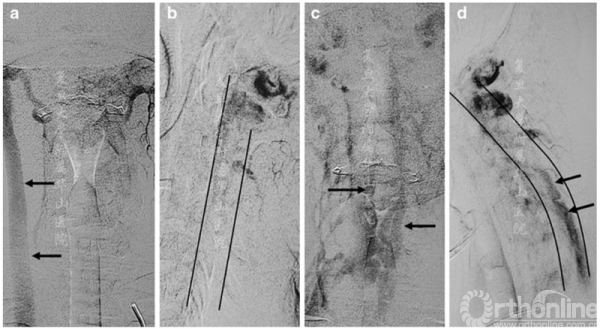

图3 左侧椎体血管造影晚期静脉相:前后位(a,c)和侧位(b,d),中立位(a,b)和屈颈位(c,d)。在中立位,右颈静脉清晰可见(a中的箭头),而当硬膜外静脉丛充血时,右颈静脉变得不透明(c和d中的箭头)。在b和d中勾勒了椎管的前后轮廓

MRI(图2a,b)和CT血管造影显示屈颈时的硬膜外静脉丛明显扩张,术前进行了脑和颈部血管造影以排除血管分流(图3a-d)。屈颈时观察到静脉血从椎管外静脉流入椎管内静脉,硬膜后方静脉丛扩张。次日患者接受成功C4-C6及颈部硬膜成形术,硬膜固定至切除的椎板边缘。患者病情平稳,症状部分恢复(强度主观提高)。在为期12个月的随访中,患者的状况保持不变。